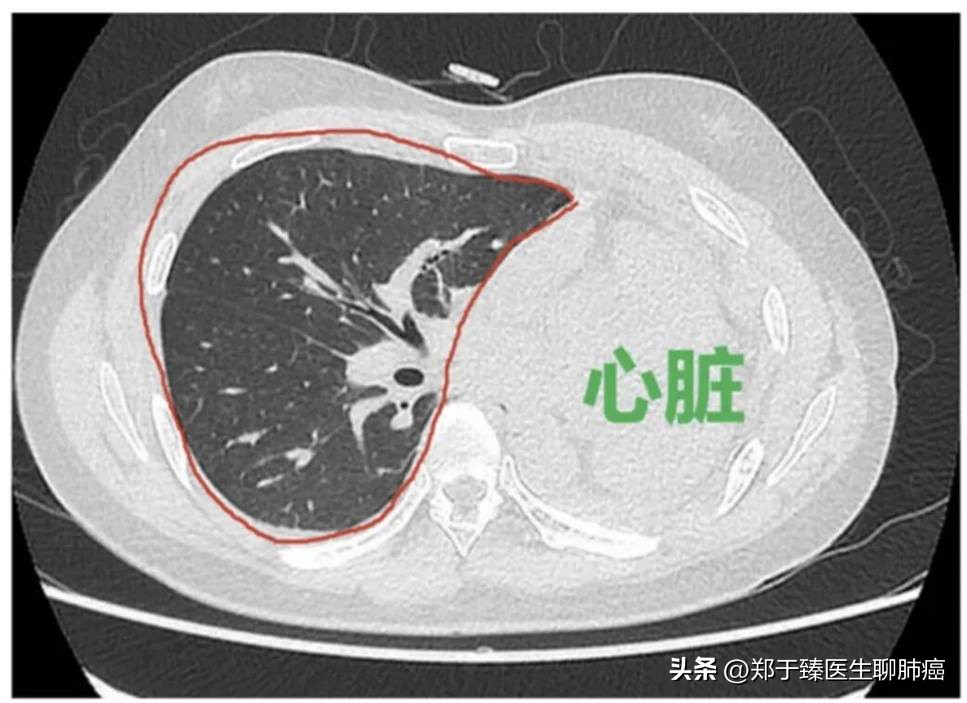

从上面这张图中,我们可以直观地感受到肺手术造成的内伤程度。

例如,左上肺切除后,下面的肺会膨胀,对侧的肺也会膨胀,推动心脏向左移位,填补左上肺切除后的空缺。

▲ 左上肺叶切除的半年恢复

这是一个左上肺叶切除术后的患者。手术后,随着恢复时间的延长,左肺和右肺都开始膨胀。

到了术后半年,残存的肺部基本填满了整个胸腔,心脏(红色轮廓部分)也被推动到更靠左的位置,表明肺部已经接近涨满,完成了代偿。